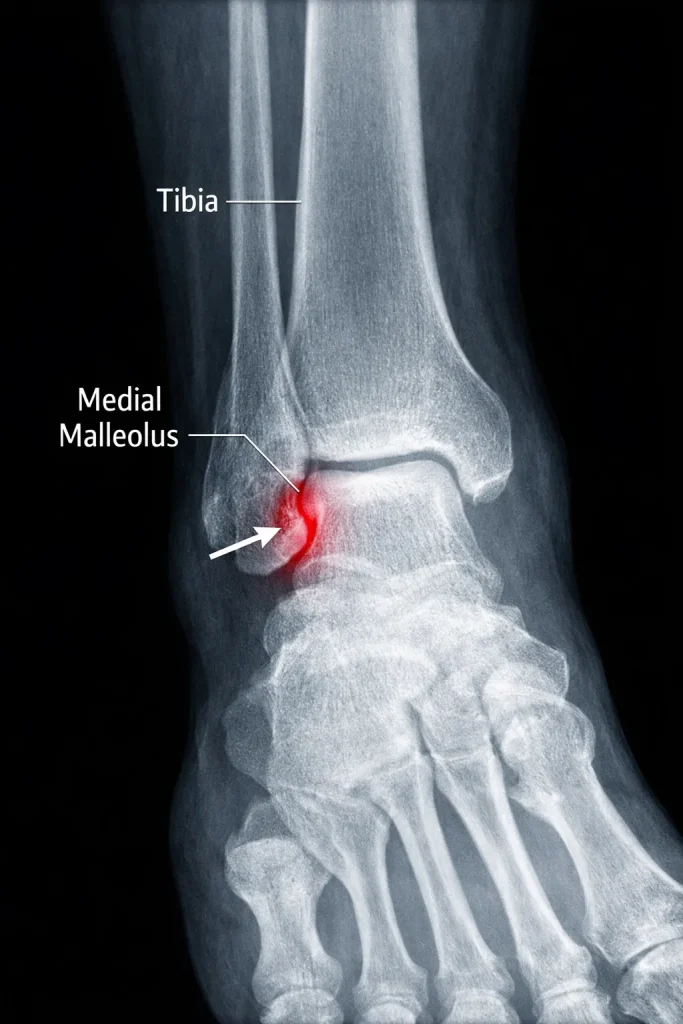

X-ray Imaging

X-rays are the primary diagnostic tool. Standard views include:

- AP view

- Lateral view

- Mortise view

These help determine fracture pattern and displacement.

Anatomy of the Medial Malleolus

The medial malleolus is part of the distal tibia and serves as an attachment for the strong deltoid ligament, which stabilizes the ankle joint.

The medial malleolus is the bony prominence on the inner side of your ankle. It forms part of the ankle joint and helps stabilize the talus bone during walking and weight-bearing.